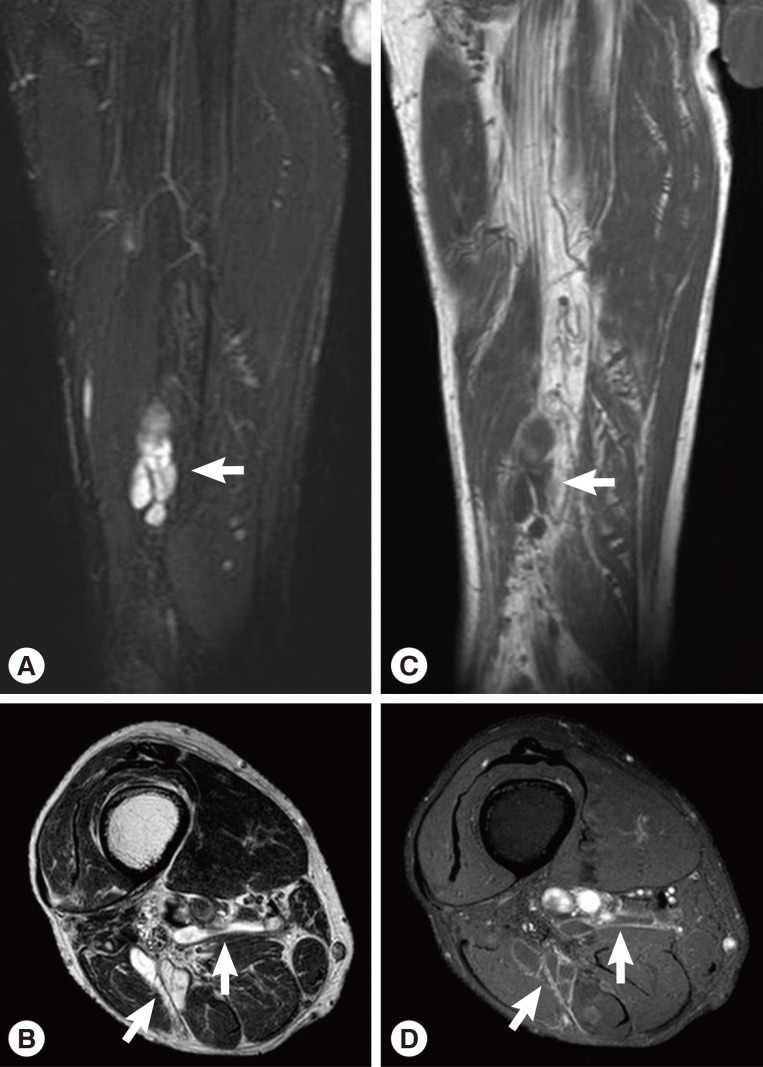

Routine laboratory test results were unremarkable, and no eosinophilia was noted. Plain radiographs of the right leg revealed multiple calcifications extending from the medial part of the knee to the calf. Ultrasonography revealed a heterogeneous, hyperechoic mass with a hypoechoic tubular lesion in the gastrocnemius muscle (Fig. 1), and MRI revealed multiple tubular and cystic lesions in the gastrocnemius muscle. The lesions showed high signal intensity on T2-weighted images and multilobulated, peripheral enhancing low signal intensity on T1-weighted images (Fig. 2). The patient was a farmer, and he had occasionally ingested raw snake meat when he was young. Preoperative serodiagnosis of human sparganosis by using a monoclonal antibody-based competitive ELISA was positive (3.79 in OD value) (negative < 1.00).

Fig. 2

MRI showing multiple tubular and cystic lesions of high signal intensity on coronal and axial T2-weighted images (arrows) (A, B) and multilobulated, peripheral enhancing low signal intensity on coronal and axial T1-weighted images (arrows) (C, D) in the gastrocnemius muscle.

Fig. 2 MRI showing multiple tubular and cystic lesions of high signal intensity on coronal and axial T2-weighted images (arrows) (A, B) and multilobulated, peripheral enhancing low signal intensity on coronal and axial T1-weighted images (arrows) (C, D) in the gastrocnemius muscle.